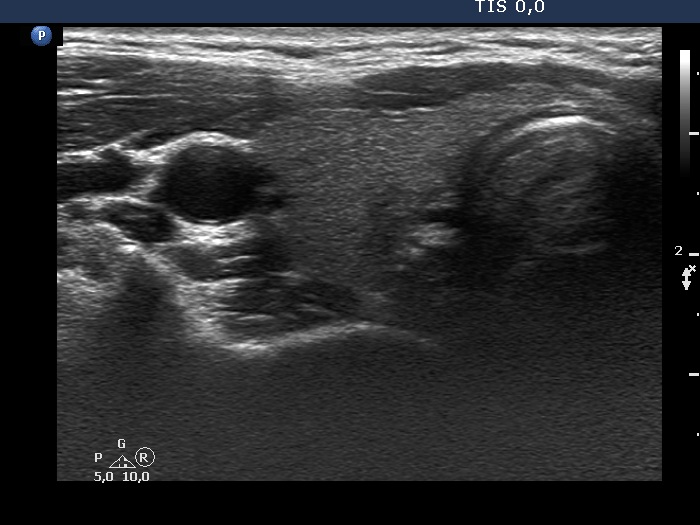

Four months after the previous examination (third row of images):

Clinical presentation: The neck complaints and elevated body temperature have immediately ceased and did not recur.

Palpation: no abnormality.

Laboratory tests: TSH 1.14 mIU/L, FT4 12.2 pM/L, CRP 0.49 mg/L, aTPO 0.6 U/mL.

Ultrasonography: The extent of hypoechoic areas has decreased. The left lobe became significantly smaller. The vascularity remained scanty.

Suggestion. Follow-up in six months.